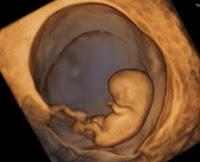

Una de las complicaciones mas frecuentes sobre todo durante el primer trimestre del embarazo es la AMENAZA DE ABORTO definida como presencia de SANGRADO DE ORIGEN INTRAUTERINO antes de la semana 20º de gestación, con o sin contracciones uterinas pero en AUSENCIA DE DILATACIÓN CERVICAL. Cuando la gestación sobrepasa las 6 semanas, la ecografía DEBE revelar que el EMBRIÓN MUESTRA LATIDO CARDÍACO. ES IMPORTANTE QUE SEPAS QUE NO ES SINÓNIMO DE ABORTO!!!

- La ecografia: es instrumento muy útil para valorar el saco gestacional a partir de la 5ta semana, y el bienestar del embrión (feto) a partir de la 6ta semana de gestación, así como la longitud del cuello uterino y probable presencias de miomas uterinos, hematomas o desprendimientos del saco gestacional que podrían ser la causa del sangrado.